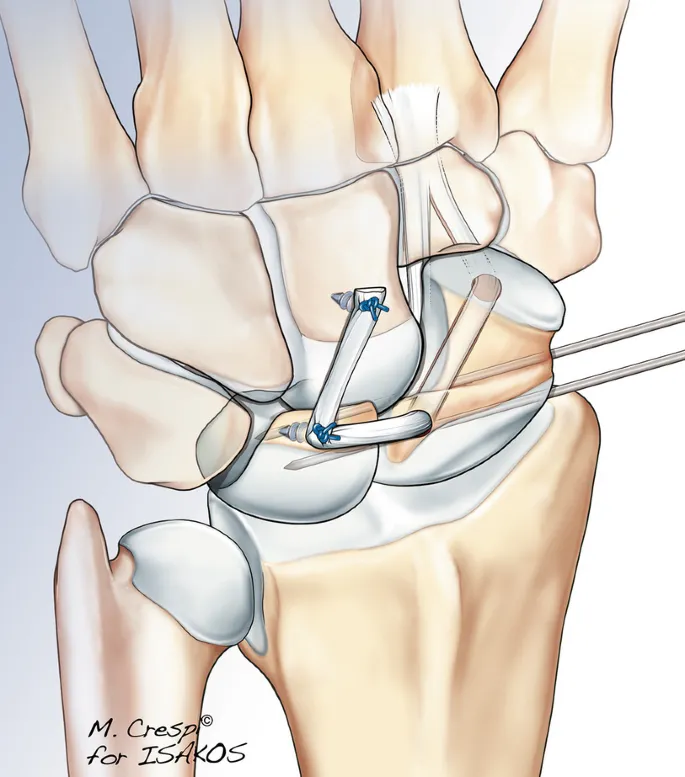

- Hechten van het ligament: Als het letsel kort geleden gebeurde, kan de chirurg proberen de uiteinden van het scapholunaire ligament weer aan elkaar te hechten en de polsbotjes tijdelijk met pinnetjes vast te zetten zodat de band kan genezen. Scafolunaire letsels worden tegenwoordig in de meeste gevallen via arthroscopie of kijkoperatie behandeld. Hierdoor kan het beschadigde ligament gehecht of verstevigd worden zonder grote littekens. Dit scheelt in de revalidatie en zorgt voor minder verstijving van de pols nadien.

- Reconstructie :Is de scheur ouder of de kwaliteit van het weefsel slecht, dan wordt vaak een reconstructie uitgevoerd. De techniek gebruikt een strookje van een polspees (bijvoorbeeld een deel van een buigpees) om de functie van het gescheurde ligament over te nemen en scaphoid en lunatum weer bij elkaar te houden.